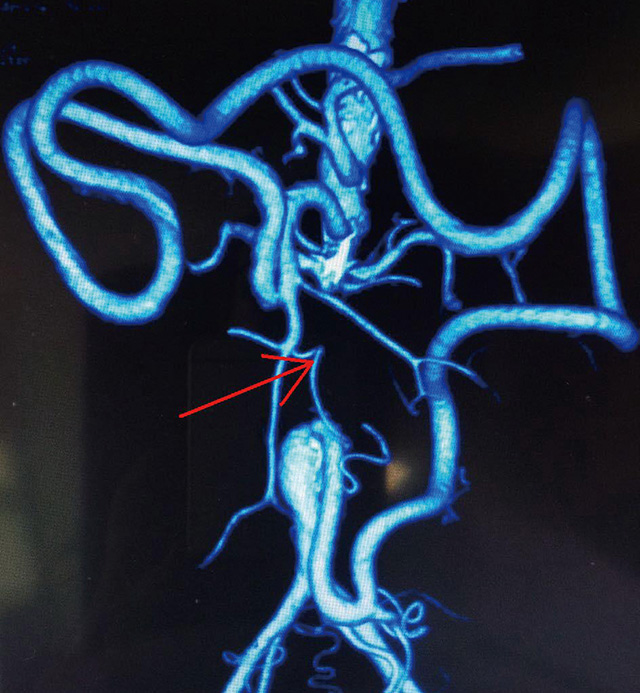

入院后,普外科首席專家李森教授和主管醫(yī)生為孫先生做了詳細的查體,發(fā)現(xiàn)病人雙下肢皮溫較低,右足踇趾、中趾缺如,中趾處創(chuàng)面觸痛明顯,雙足血供差,可見多處潰瘍愈合疤痕,雙側(cè)股動脈、腘動脈、脛后動脈、足背動脈搏動未觸及。動脈強化造影示腹主動脈及雙側(cè)髂總動脈完全閉塞,僅有少量交通支與遠側(cè)髂外動脈相通。明確診斷為腹主動脈硬化閉塞癥。根據(jù)各項相關(guān)檢查證實,病情是在腹主動脈硬化閉塞癥導(dǎo)致的嚴重肢體缺血癥狀,必須行血管轉(zhuǎn)流術(shù),才能獲得較好的治療效果,否則只能截肢。

(病人術(shù)前的相關(guān)影像學(xué)檢查資料:紅色箭頭處顯示主動脈腎下段充盈缺損,周圍側(cè)支循環(huán)建立)